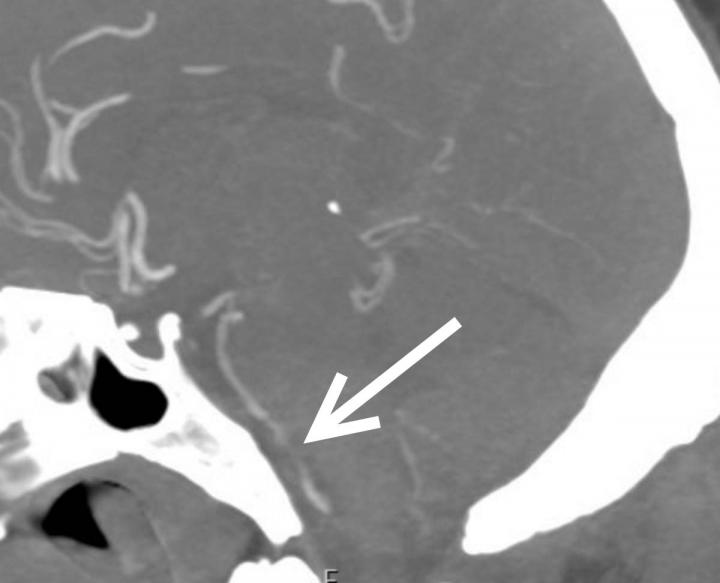

Out of 81 patients with brain scans, 18, or just over one in five, had findings that were considered emergency or critical, including strokes, brain bleeds and blocked blood vessels. At least half the patients had pre-existing histories of high blood pressure and/or type 2 diabetes. Three patients with emergent/critical findings died while admitted.

The exact mechanisms for COVID-19's harmful neurological effects are not known and may involve multiple factors, although a popular theory holds that inflammation associated with the infection is the primary culprit. In the study, blood markers of inflammation were high in people with critical results.